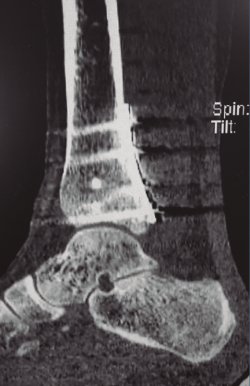

Este abordaje permite la reducción anatómica de fracturas con fragmentos posteromediales difíciles de controlar desde un abordaje posterolateral (Figura 4) (y que son fundamentales para la estabilidad rotacional del tobillo, al insertarse en estos la porción más profunda del ligamento deltoideo), si bien es cierto que desde la vía posterolateral podría accederse también a estos fragmentos posteromediales (mediante la retracción agresiva del FHL), pero con el único objetivo de evitar una segunda incisión posteromedial.

Figura 4. Tomografía computarizada postoperatoria de una fractura de tipo II de Haraguchi y de tipo 3 de Bartoníček tratada mediante osteosíntesis con placa de soporte por vía posteromedial.